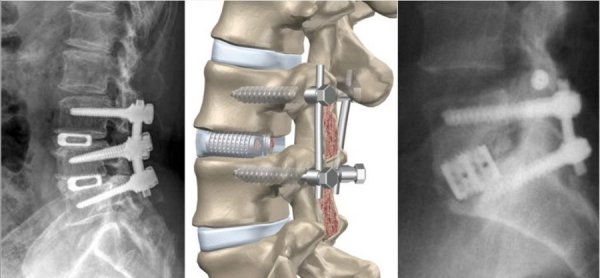

К хирургической операции прибегают в том случае, если патология на 2 стадии и позднее. Чрезмерное смещение позвонка опасно сдавливанием спинного мозга, поэтому провести декомпрессию стоит как можно скорее. Вмешательство позволит также стабилизировать позвоночник.

Основным популярным способом является лапароскопия. Она отличается минимальной травматичностью и небольшими осложнениями после операции. Через небольшой разрез запускается зонд, который обеспечивает видеосъемку для полной видимости. В процессе не задеваются мягкие ткани, волокна мышц или связки, а значит кровотечение небольшое. После операции пациент может как можно скорее вернуться к нормальной жизни.

Пораженный позвонок замещается вентральной пластиной, или фиксируется винтами, замещается титановыми имплантами. Подбирается вид материала и подходящий вариант индивидуально, исходя из особенностей развития болезни.